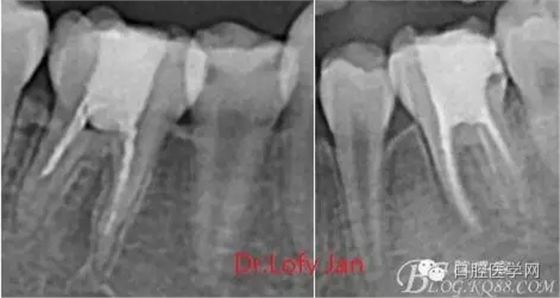

曲面斷層片在未試尖根管治療中的病例整理

前言:自己做的一些曲面斷層片在未試尖根管治療中的病例整理,發(fā)現(xiàn)問題很多包括自身的,技術(shù)的,還有設備的問題,予以總結(jié)整理并期待進一步提高。

根管治療術(shù)是牙體牙髓疾病治療中最復雜和最關(guān)鍵的治療項目。根管充填材料抵達根尖、并能嚴密堵塞根尖孔,是確保根管治療效果的關(guān)鍵指標。為了保證根管充填到位,醫(yī)生需要在術(shù)前照牙片以了解牙根根管的數(shù)量、彎曲程度和長度,在術(shù)中有時需要插針照牙片來精確測量根管長度,術(shù)后必須照牙片以確定是否根管充填到位,如果欠填或超填,就需要重新充填、重新照牙片確認,直到根管充填到位。所以,在患者接受根管治療時有時會反復照牙片。

病例分析:曲面斷層片在x線輔助診斷與檢查中目前大多數(shù)文獻和著作都建議只能作為初診拍片檢查手段,不能作為終末疾病的確診與手術(shù)療效的評價指標,臨床大部分中小型門診都因為設備不齊全導致信息偏差很大。